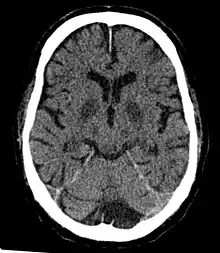

- Cerebral infarction – A "stroke", caused by complete oxygen deprivation due to an interference in cerebral blood flow which affects multiple areas of the brain.